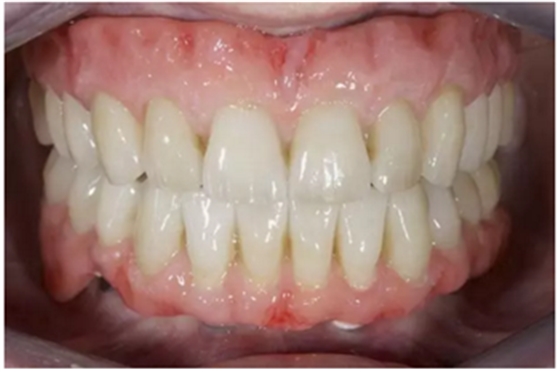

手術(shù)后16周最終修復(fù):上頜覆蓋義齒是卡扣在鈦桿卡(IBO)上,義齒牙冠部分是由二矽酸鋰玻璃陶瓷制作的單冠。下頜的氧化鋯種植長橋(PIB)上同樣也制作二矽酸鋰玻璃陶瓷的單冠并進(jìn)行粘接。